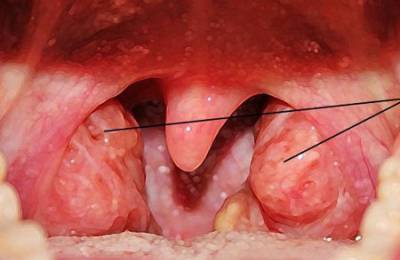

Температура может колебаться от 37,3 до 39 градусов, либо быть в норме. Катаральная ангина может сопровождаться ознобом, судорогами. Небные миндалины увеличиваются, отекают, наблюдается гиперемия дужек слизистой оболочки глотки;

Фолликулярная: характеризуется наличием гнойного воспаления лимфоидных образований глотки (фолликулов) в виде отдельных очагов нагноения на небных, трубных, глоточных или язычных миндалинах, а также увеличенных шейных регионарных лимфоузлов.

Заболевание сопровождается резким повышением температурных показателей, болью в горле, слабостью. Ребенок становится беспокойным, плачет, отказывается от еды, не хочет ничего делать. Можно наблюдать затруднение речи, наличие серого налета на языке;

Лакунарная: проявляется стремительно, характеризуется недомоганием и слабостью, повышением температуры тела до 39 градусов, ознобом, нарушением сна, потерей аппетита, уменьшением активности, неприятными ощущениями в гортани.

Симптомы ангины у детей: воспаление и увеличение лимфоузлов, отек горла, наличие гнойных образований белого или желтого цвета на миндалинах, либо полного покрытия налетом поверхности (одной или обеих миндалин);